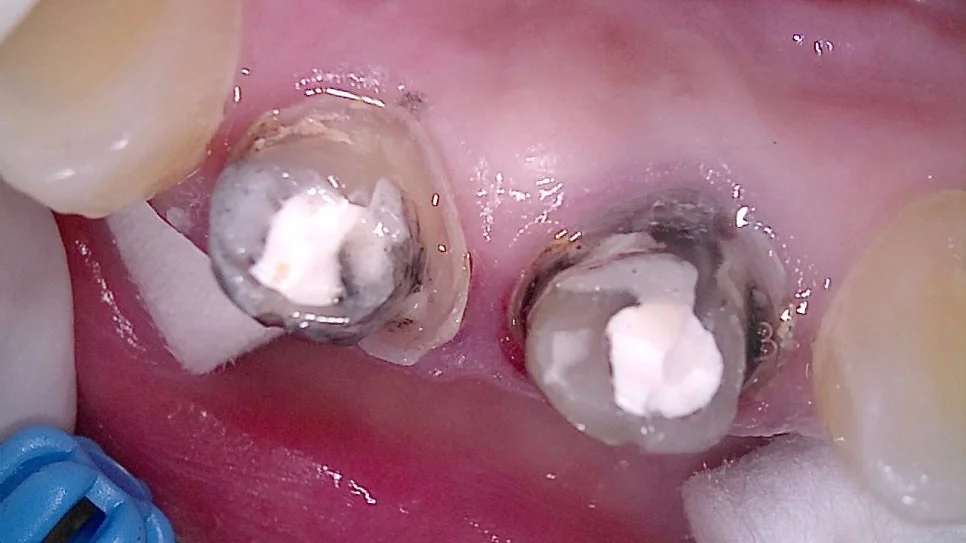

안쪽을 확인해봐도 오염이 심하게 진행된 상태가 보여집니다.

재신경치료 — 신경관 확대 및 소독 과정 엑스레이

각 신경관이 뿌리 끝까지 제대로 이어져 있는지 경로를 먼저 확보하고, 안쪽에 남아있는 염증·세균을 없애기 위해 충분히 넓히고 소독해 줍니다.